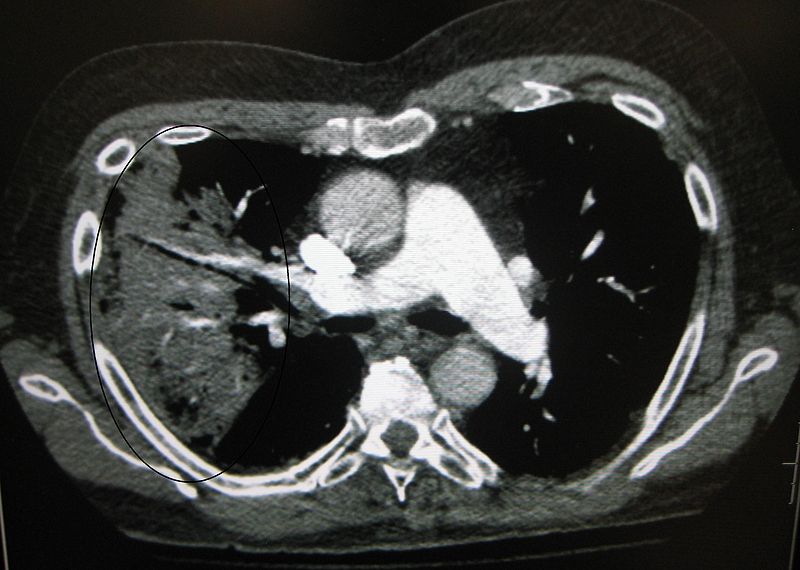

Diagnosis Of Pneumonia Benzos And Pneumonia Our study suggested that bzd use in osa patients increased the risk of acute respiratory failure. We found that the risk of pneumonia among participants taking benzodiazepines was attenuated and no longer statistically. The possible association of benzodiazepine (bzd) and benzodiazepine related drugs (bzrd) use with pneumonia risk has received increasing. Current or recent exposure to bzrd is associated with. Benzos And Pneumonia.